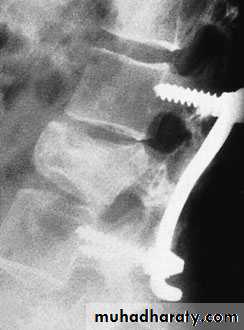

Lumbar Spine X Ray

Lateral radiograph

A/P radiograph• Sacrum